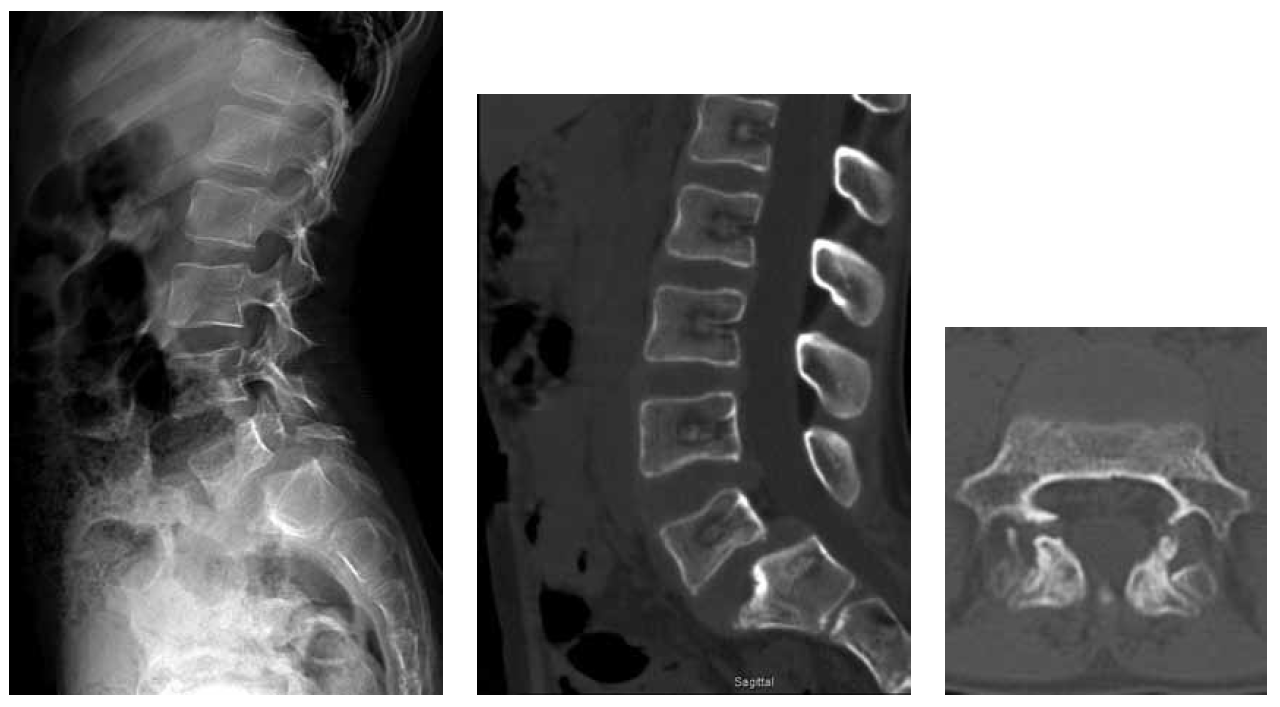

According to the radiological data of the lumbar spine, spondylolisthesis of degree 2 L5 was detected (Fig. 1). As observed on the MSCT of the lumbar spine (see Fig. 1), there was a congenital malformation, a bilateral slit-like bone defect in the inter-articular part of the L5 arch. Spina bifida posterior of L5. True spondylolisthesis of L5 of the degree 2. Deformity of the intervertebral disk L5–S1 and the cranial part of the body S1.

Fig. 1. MSCT of the lumbar spine before surgery

After clinical, neurological, and instrumental examinations, diagnoses of dysplastic spondylolisthesis of L5 of degree 2 (44%), bilateral foraminal stenosis of L5–S1, segmental instability of L5–S1, bilateral dynamic compression syndrome of L5 roots, and lumbodynia syndrome were established.